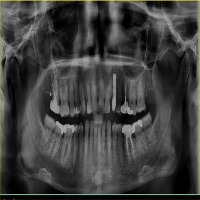

vzrad2 Computer Vision Project

Arshs Workspace Radio

downloadsClasses (93)

Amalgam filling

Bone Loss

Calculus

Caries

Cavity

Composite filling

Crown

Cyst

Implant

Periapical lesion

Root canal filling

A description for this project has not been published yet.